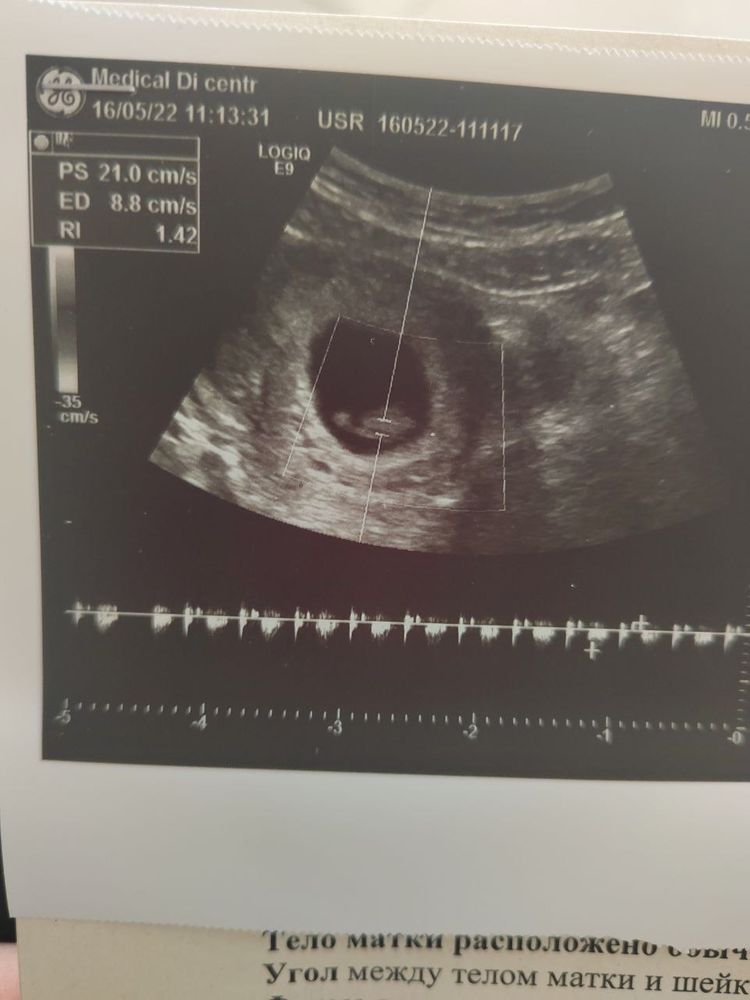

1. В понедельник пошла на УЗИ слушать сердечко) Нашли! Но в этот раз попала к другой узистке, (тот, к которому хотела пойти, ушел в отпуск) - это была пожилая тетечка, видно, что опытная. Она не стала смотреть меня вагинально, только по животу сверху, сказала "лучше туда лишний раз не лезть". Я немного удивилась, думала, на таком сроке только вагинально смотрят, к тому же приехала на пустой мочевой, что там можно увидеть-то? Ан нет, увидела сразу и эмбрион, и сердечко) Всё прошло очень быстро. Сердечко прям видно как мигает на экране) и включила послушать, буквально 7 секунд, так громко, быстро-быстро и четко! Лежала и улыбалась. Думала, расплачусь, но даже не успела, всё очень быстро прошло) Либо видать я не особо эмоциональна (хотя это я же потом дома смотрела на ютубе нарезки видео типа "отцы впервые держат на руках новорожденных детей" и рыдала как бегемот полчаса)

ЧСС точное не замеряли, врач сказала просто, что всё у вас хорошо, идите вставать на учет в ЖК. КТР 10 мм. Сделали фото) Но видно не очень четко, - думаю, что опять же из-за того что сверху смотрели.